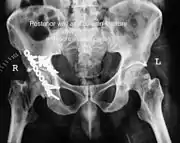

Acetabular fracture

Acetabular fracture as seen on plain X-ray

Fractures of the acetabulum occur when the head of the femur is driven into the pelvis. This injury is caused by a blow to either the side or front of the knee and often occurs as a dashboard injury accompanied by a fracture of the femur.[1]